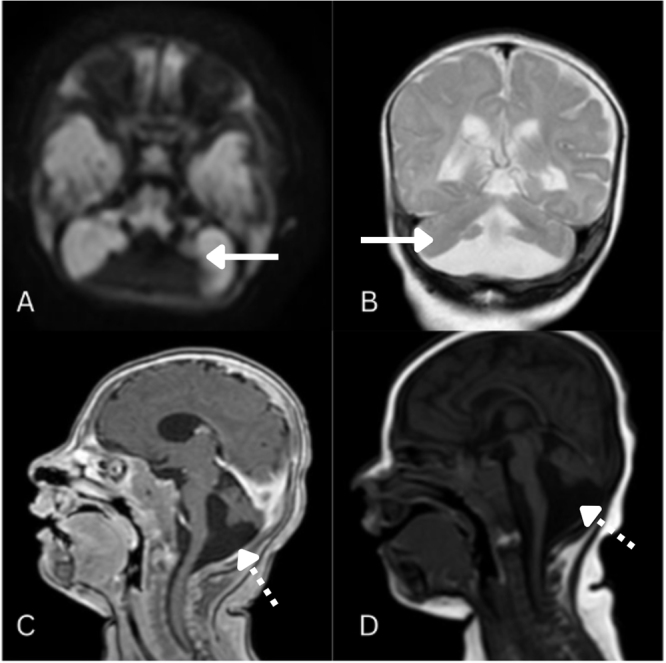

Case presentation: A 27-month-old female with recurrent seizures since infancy presented with generalized tonic-clonic movements, ocular deviation, and frothing, lasting 2 h. Examination revealed fever, tachycardia, tachypnea, and hypertonia. MRI at 5 months confirmed Dandy-Walker spectrum disorder with cerebellar vermis hypoplasia, a posterior fossa cyst, and fourth ventricle malformation. Electroencephalogram at 14 months showed diffuse encephalopathy with multifocal seizures, and fundoscopy revealed bilateral optic atrophy. TORCH (toxoplasmosis, rubella cytomegalovirus, herpes simplex, and HIV) screening was unremarkable. Despite antiseizure therapy with levetiracetam and phenytoin, persistent seizures required pediatric intensive care unit admission. Valproate (15 mg/kg/day, titrated to 20 mg/kg/day) achieved seizure control.